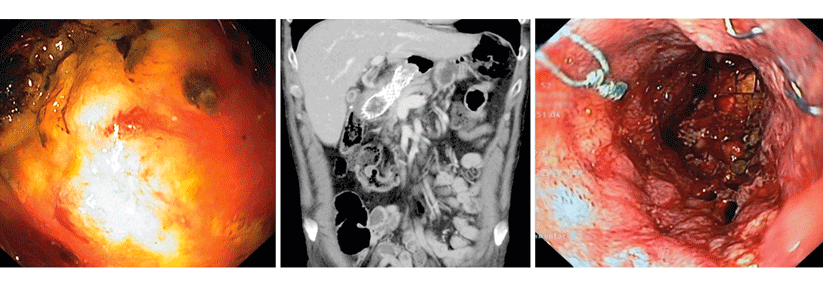

Nach wie vor wird es so sein, dass in Deutschland kein bevölkerungsbezogenes endoskopisches Screening für das Magenkarzinom erfolgen wird“, betonte Professor Dr. Tilo Andus, Klinik für Allgemeine Innere Medizin, Gastroenterologie, Hepatologie und internistische Onkologie am Klinikum Stuttgart. Allerdings soll Patienten mit fortgeschrittener Atrophie und intestinaler Metaplasie des Magens eine endo­skopische Überwachung angeboten werden. So lautet eine der Neuerungen, die in der aktualisierten S3-Leitlinie zum Magenkarzinom zu finden sind.

Die Staging-Laparoskopie verbessert die Therapieentscheidungen beim lokal fortgeschrittenen Magenkarzinom und sollte deshalb laut aktueller Leitlinienempfehlung vor Beginn der neoadjuvanten Therapie durchgeführt werden, so der Experte weiter. Bezüglich des Re-Stagings nach der neoadjuvanten Therapie wurde laut Prof. Andus eine Empfehlung aufgenommen, die in der Praxis bereits relativ häufig verwendet wurde: Zur Bewertung des Ansprechens soll nach Abschluss der neoadjuvanten Therapie ein CT und eine ÖDG durchgeführt werden.

Der Referent erinnerte zudem an die Wichtigkeit der HER2-Testung, die unbedingt erfolgen sollte. Zu beachten sei dabei, dass ausreichend Zangenbiopsien durchgeführt werden.